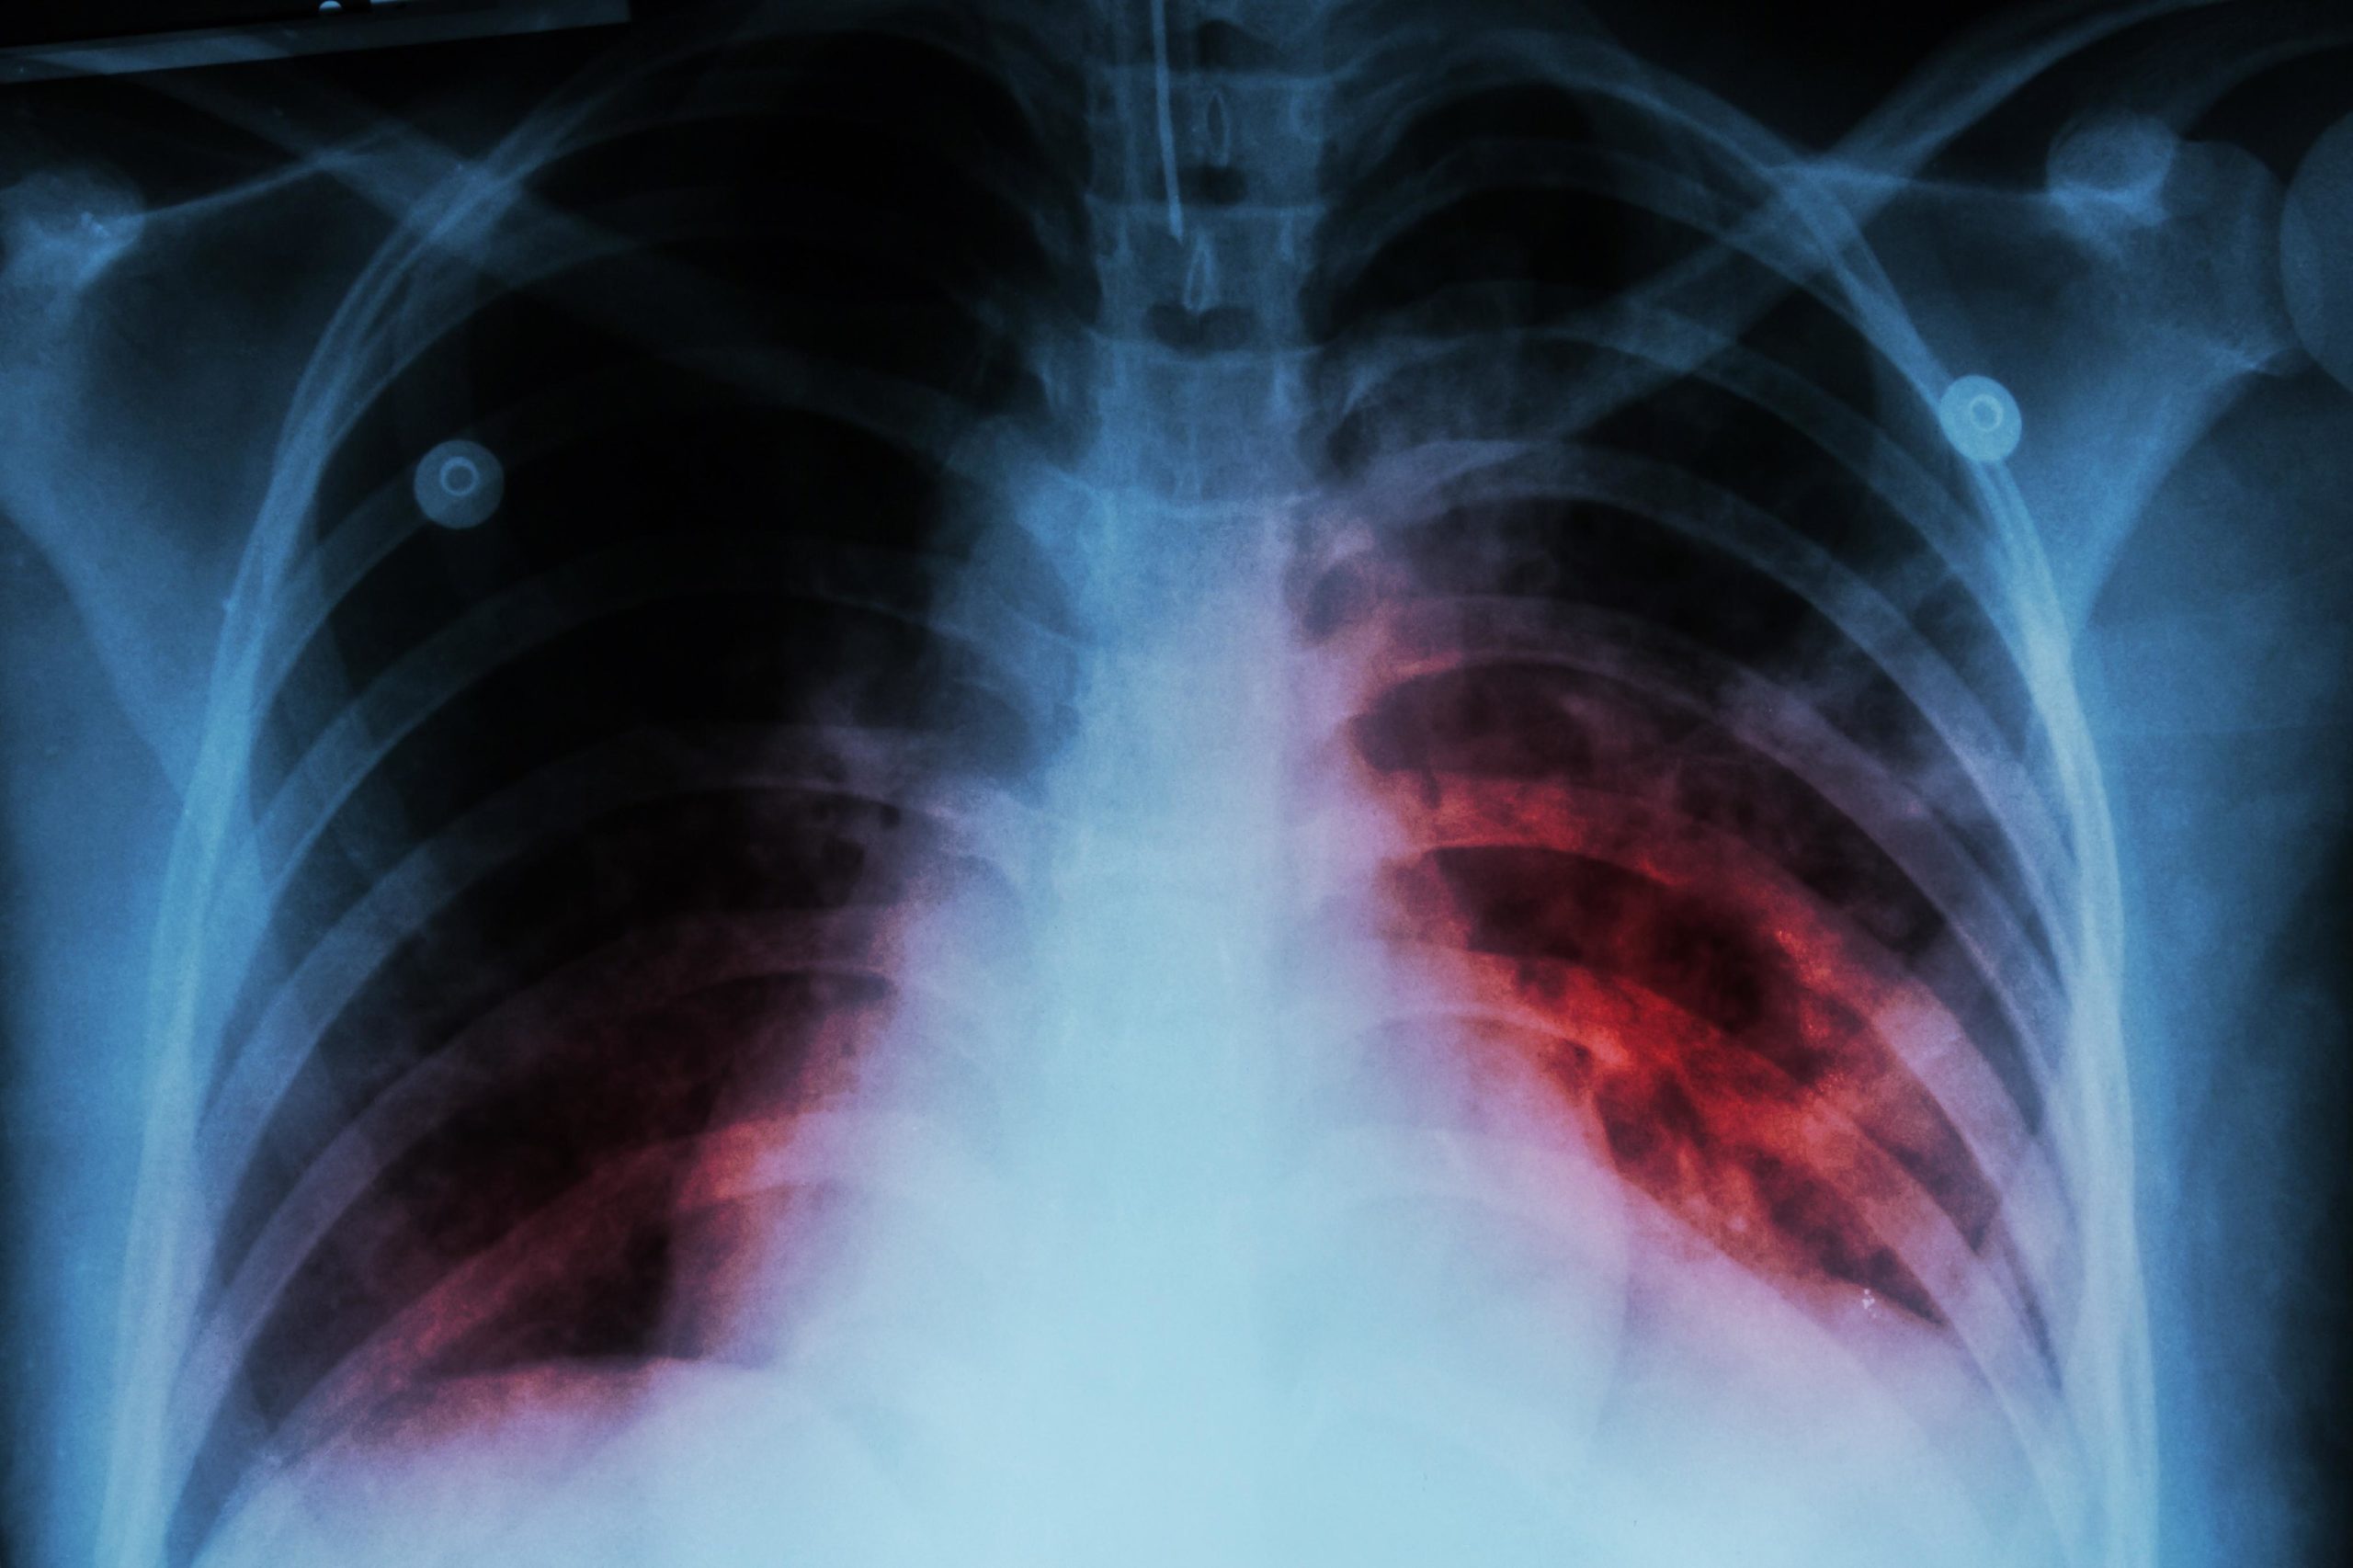

Casi 5 mil casos de tuberculosis en México, con 3 estados al frente

En la última semana de marzo se reportaron 412 nuevos casos de tuberculosis en México. Al cierre de marzo, los ...

La tuberculosis es la principal causa de muerte por un solo agente infeccioso, aún por encima del VIH Usuarios y ...